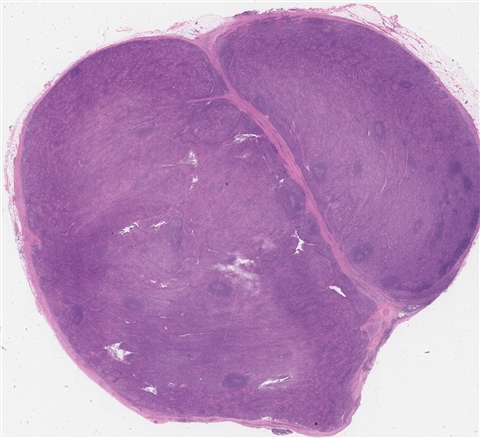

案例4 (6863)

性别:       年龄:48

患者详情: 患者4月余前体检行胸部CT检查示“右肺上叶混杂磨玻璃结节;纵隔多发肿大淋巴结可能”。3月前来我院门诊就诊,行胸部CT示“中纵隔右侧肿块,请结合穿刺;右锁骨区、纵隔及右肺门多发肿大淋巴结”。行纵隔肿块EBUS,显微镜下“见纤维素样渗出物及少量淋巴细胞、纤维样细胞及支气管上皮细胞,未见恶性依据”。行PET-CT检查示“右纵隔右侧肿块,FDG代谢增高;纵隔、双侧锁骨上小淋巴结,FDG代谢增高”。遂行纵隔肿块切除术。

大体所见: 送检“中纵隔肿瘤”一枚,大小5.5*4.5*4.0cm,包膜完整,切面灰黄质韧,中央见灰白星状瘢痕。

医院: 复旦大学附属肿瘤医院